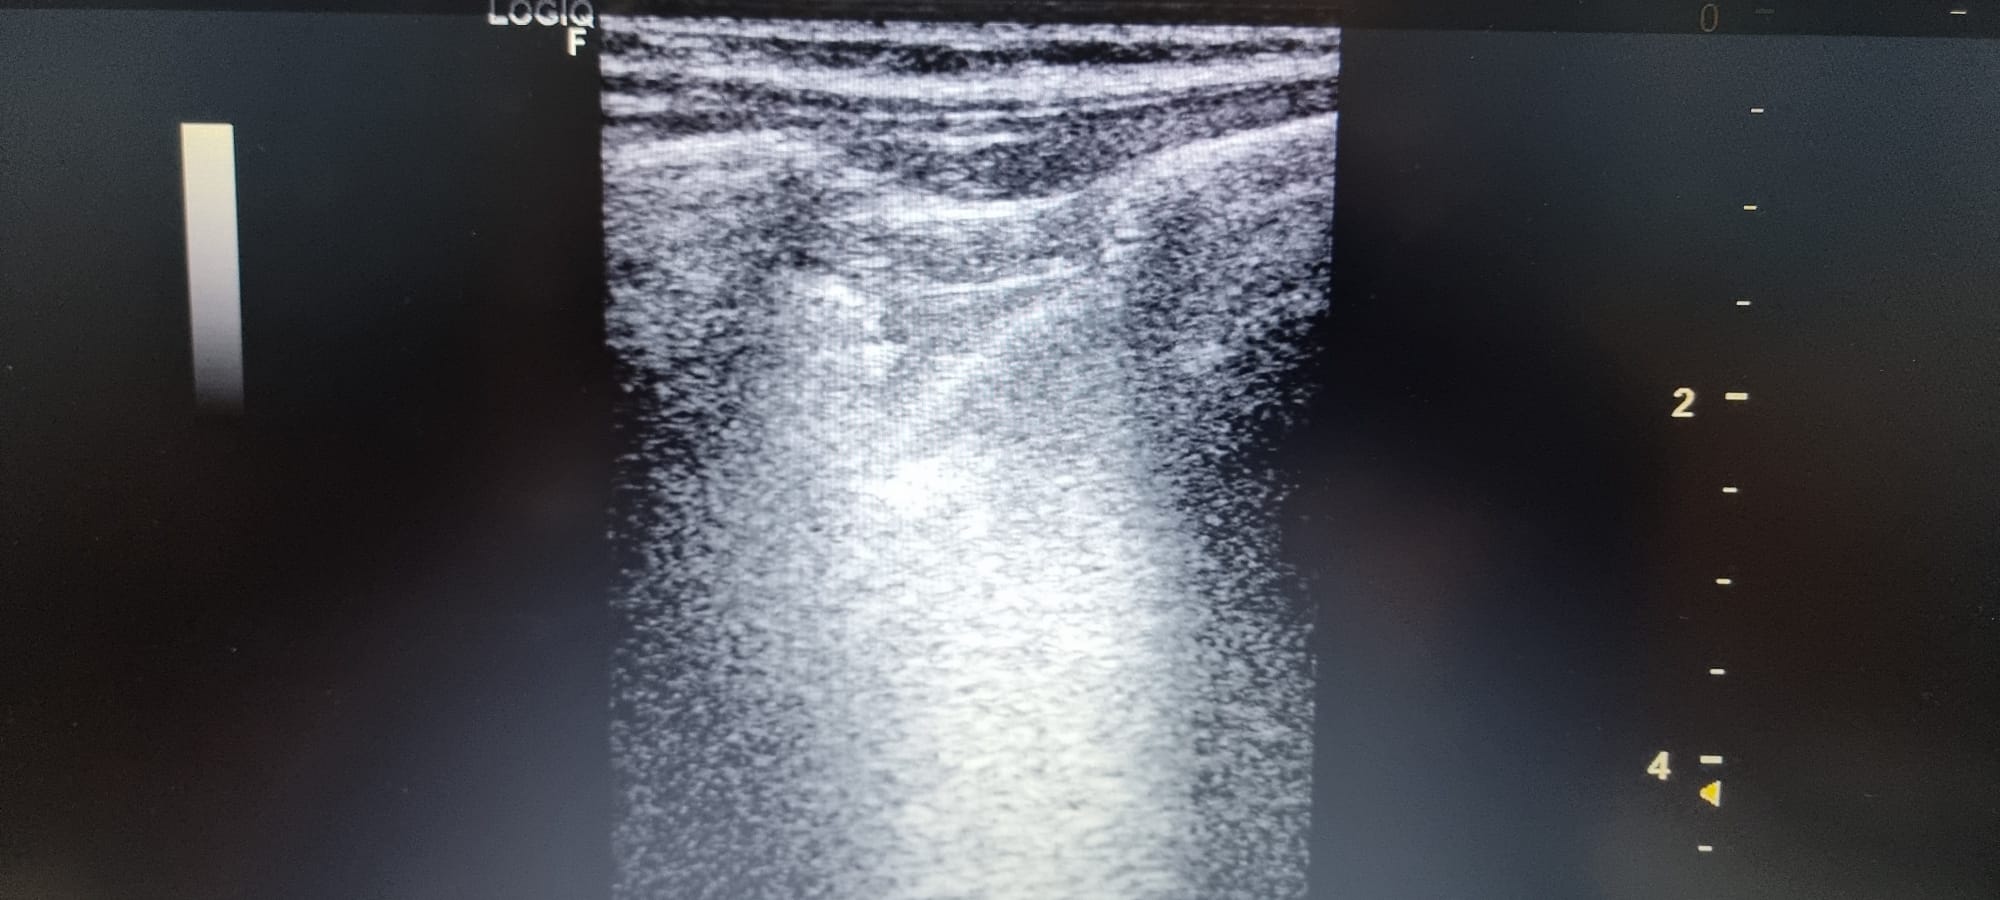

Se observa en base pulmonar izquierda defecto pleural triangullar (comparado con el contralateral).

La ecografía clínica pulmonar, nos aporta gran información que complementa la hipotesis dx, en este caso no acertada porque pensabamos mas en un TEP ya que nunca habiamos visto un derrame pleural en ecografía. Este era mínimo y no detectable con Rx Tx, con los conocimientos de la normalidad pudimos ver que había una imagen patologica comparando con el contralateral.